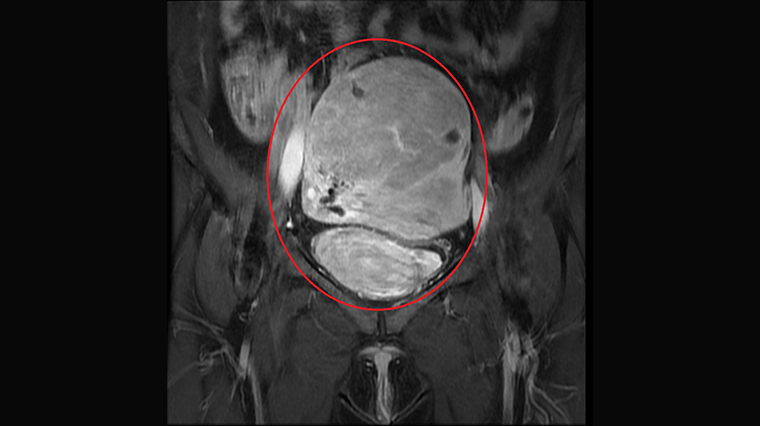

▲子宮肌腺症病灶檢查影像圖片。(圖/亞洲大學附屬醫院提供)